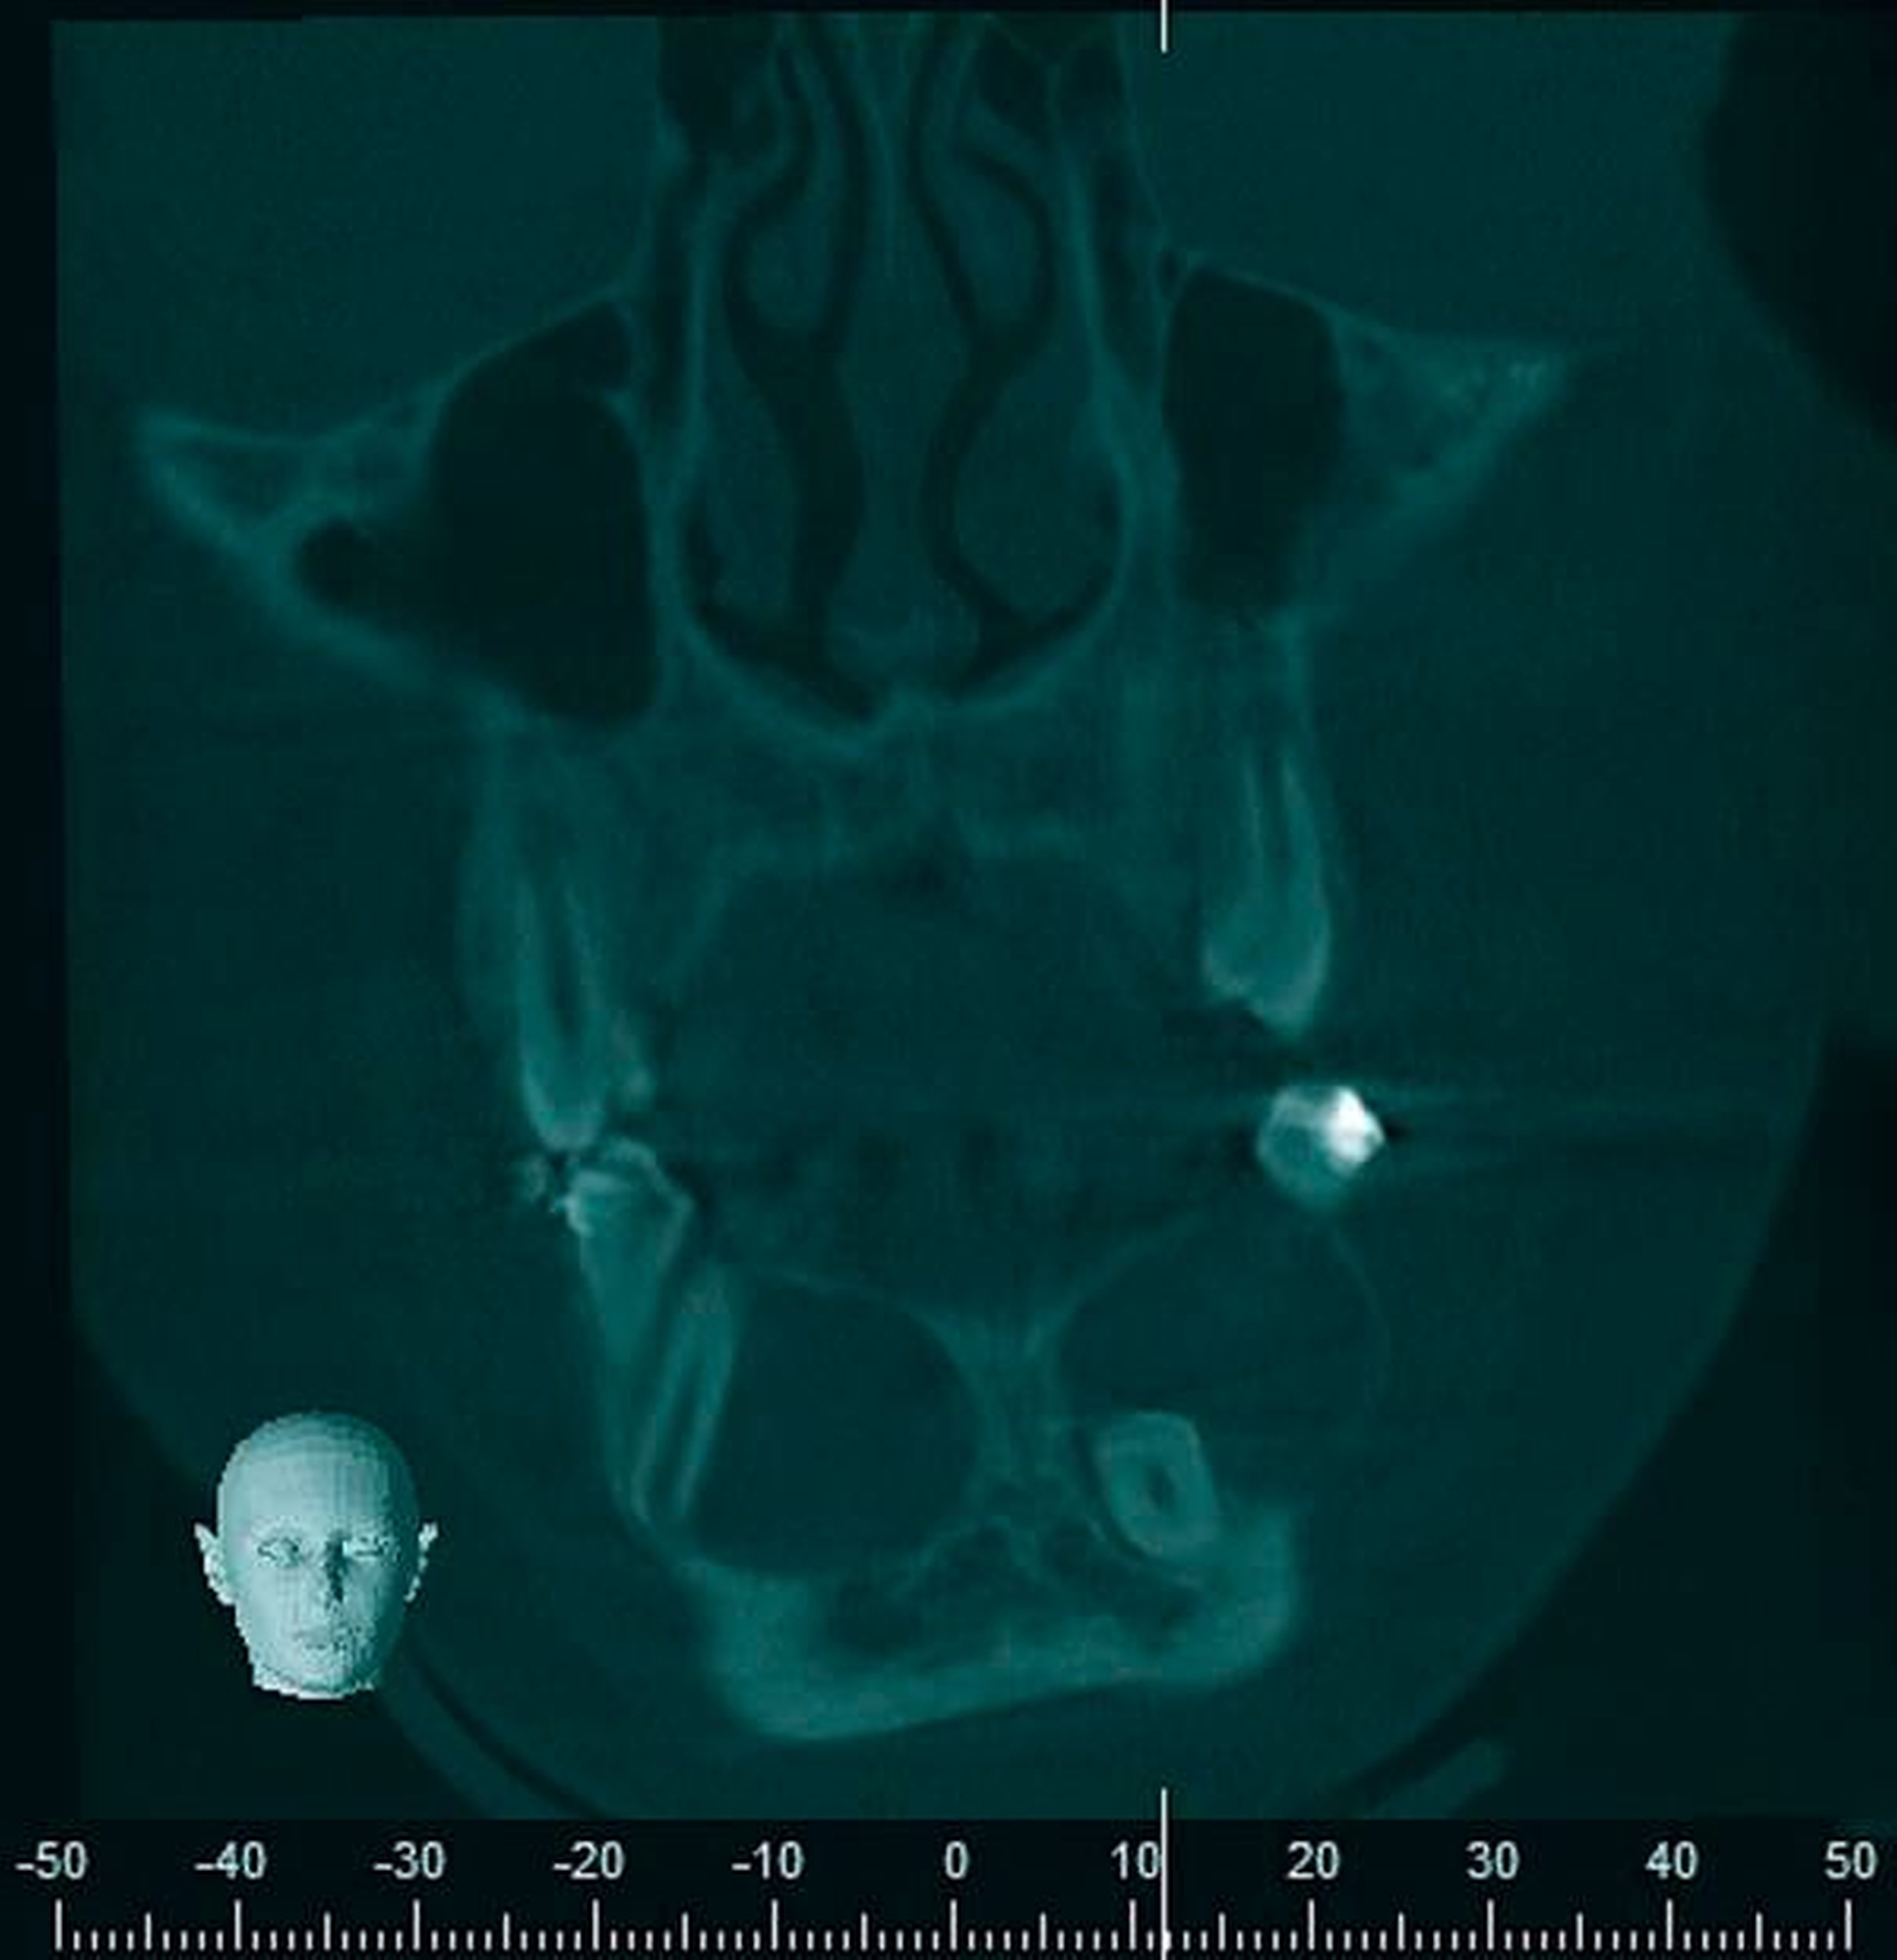

Radiologischer Befund

Im OPG (Abbildung 1) sowie in der DVT (Abbildungen 2 bis 5) imponieren zwei scharf begrenzte osteolytische Befunde im Bereich der anterioren Mandibula regio 34–32 und 41–43. Der retinierte Zahn 33 liegt basal im Lumen der Aufhellung.

Eine dreidimensionale Bildgebung zur Evaluation der Ausdehnung des Befunds und zur möglichen Beteiligung von Nachbarstrukturen ist sinnvoll. Hierfür sind DVT oder CT im Niedrigdosisprotokoll geeignet.